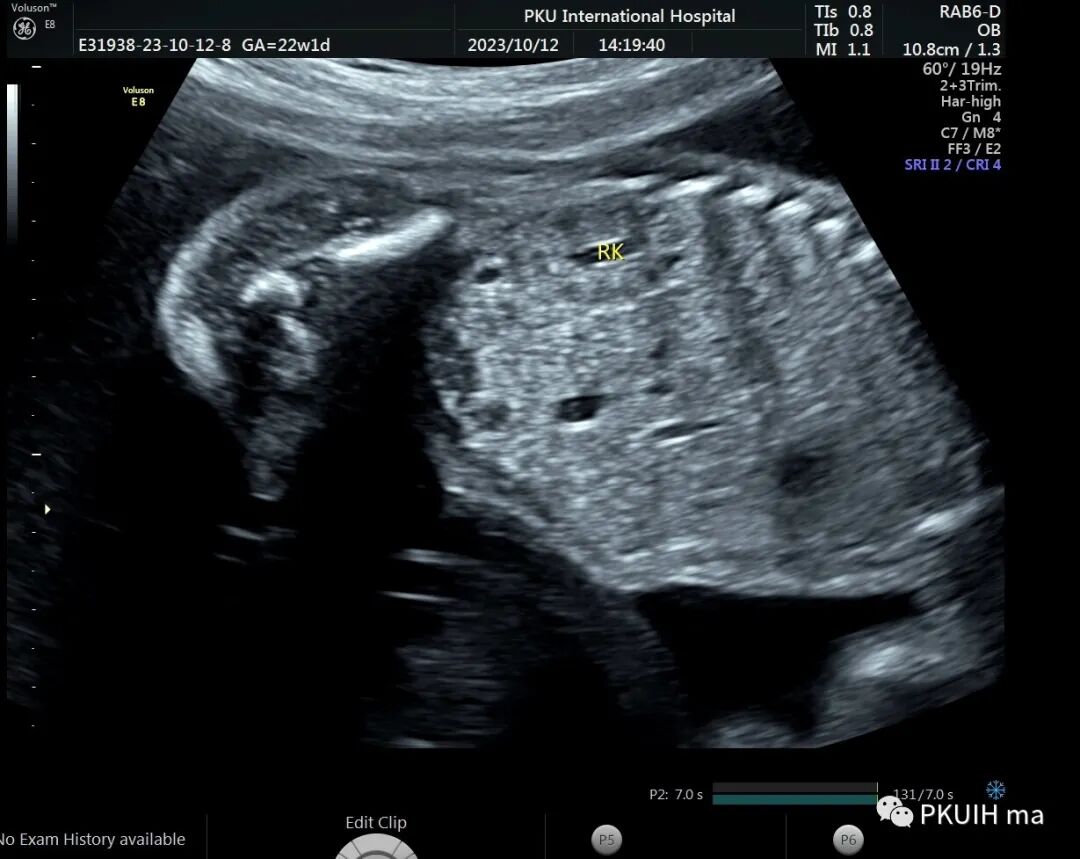

今天看到一22周的胎儿,一侧肾区未见肾脏结构,肾上腺呈平卧征,肾动脉也未显示,在盆腔见到一个发育不良的肾脏回声。

右肾大小位置正常,右肾动脉可见,左肾动脉缺如,正常的左肾区未见肾组织回声,可见肾上腺平卧。于膀胱后上方见一肾组织回声,大小约1.5x1.4x1.0cm,皮髓质分界欠清晰,血供来源于髂动脉。